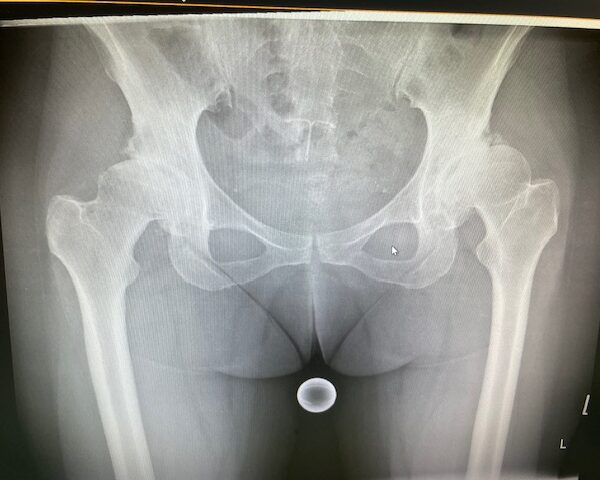

Η ασθενής είχε απευθυνθεί από χρόνια σε πολλούς συναδέλφους ορθοπεδικούς στην Ελλάδα και το εξωτερικό. Είχε προηγηθεί ήδη διεξοδικός απεικονιστικός έλεγχος (ακτινογραφίες λεκάνης και ισχίου, αξονική και μαγνητική τομογραφία).

Το 2024 όταν πλέον η ασθενής απευθύνθηκε σε εμένα, ακολούθησε εκ νέου ακτινογραφικός έλεγχος ώστε να μπορέσει να πραγματοποιηθεί ο προεγχειρητικός ψηφιακός σχεδιασμός του Χειρουργείου.

Ο ακτινογραφικός έλεγχος έδειχνε προχωρημένες εκφυλιστικές αλλοιώσεις και αλλοίωση της ανατομίας της κοτύλης και του μηριαίου.